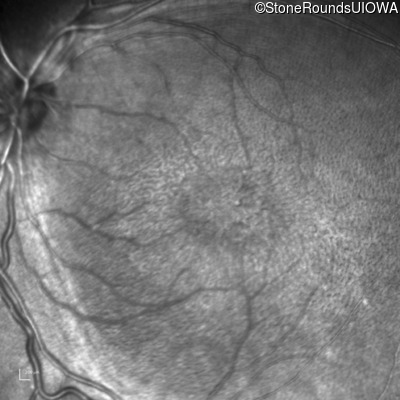

XL Retinoschisis (IIIB1)

Age at visit: 6 years

OD OS

This 6 year old boy began sitting very close to the television at age 2.

Diagnosis & molecular findings

XL Retinoschisis RS1 Tyr93Stop TAT>TAG   XL